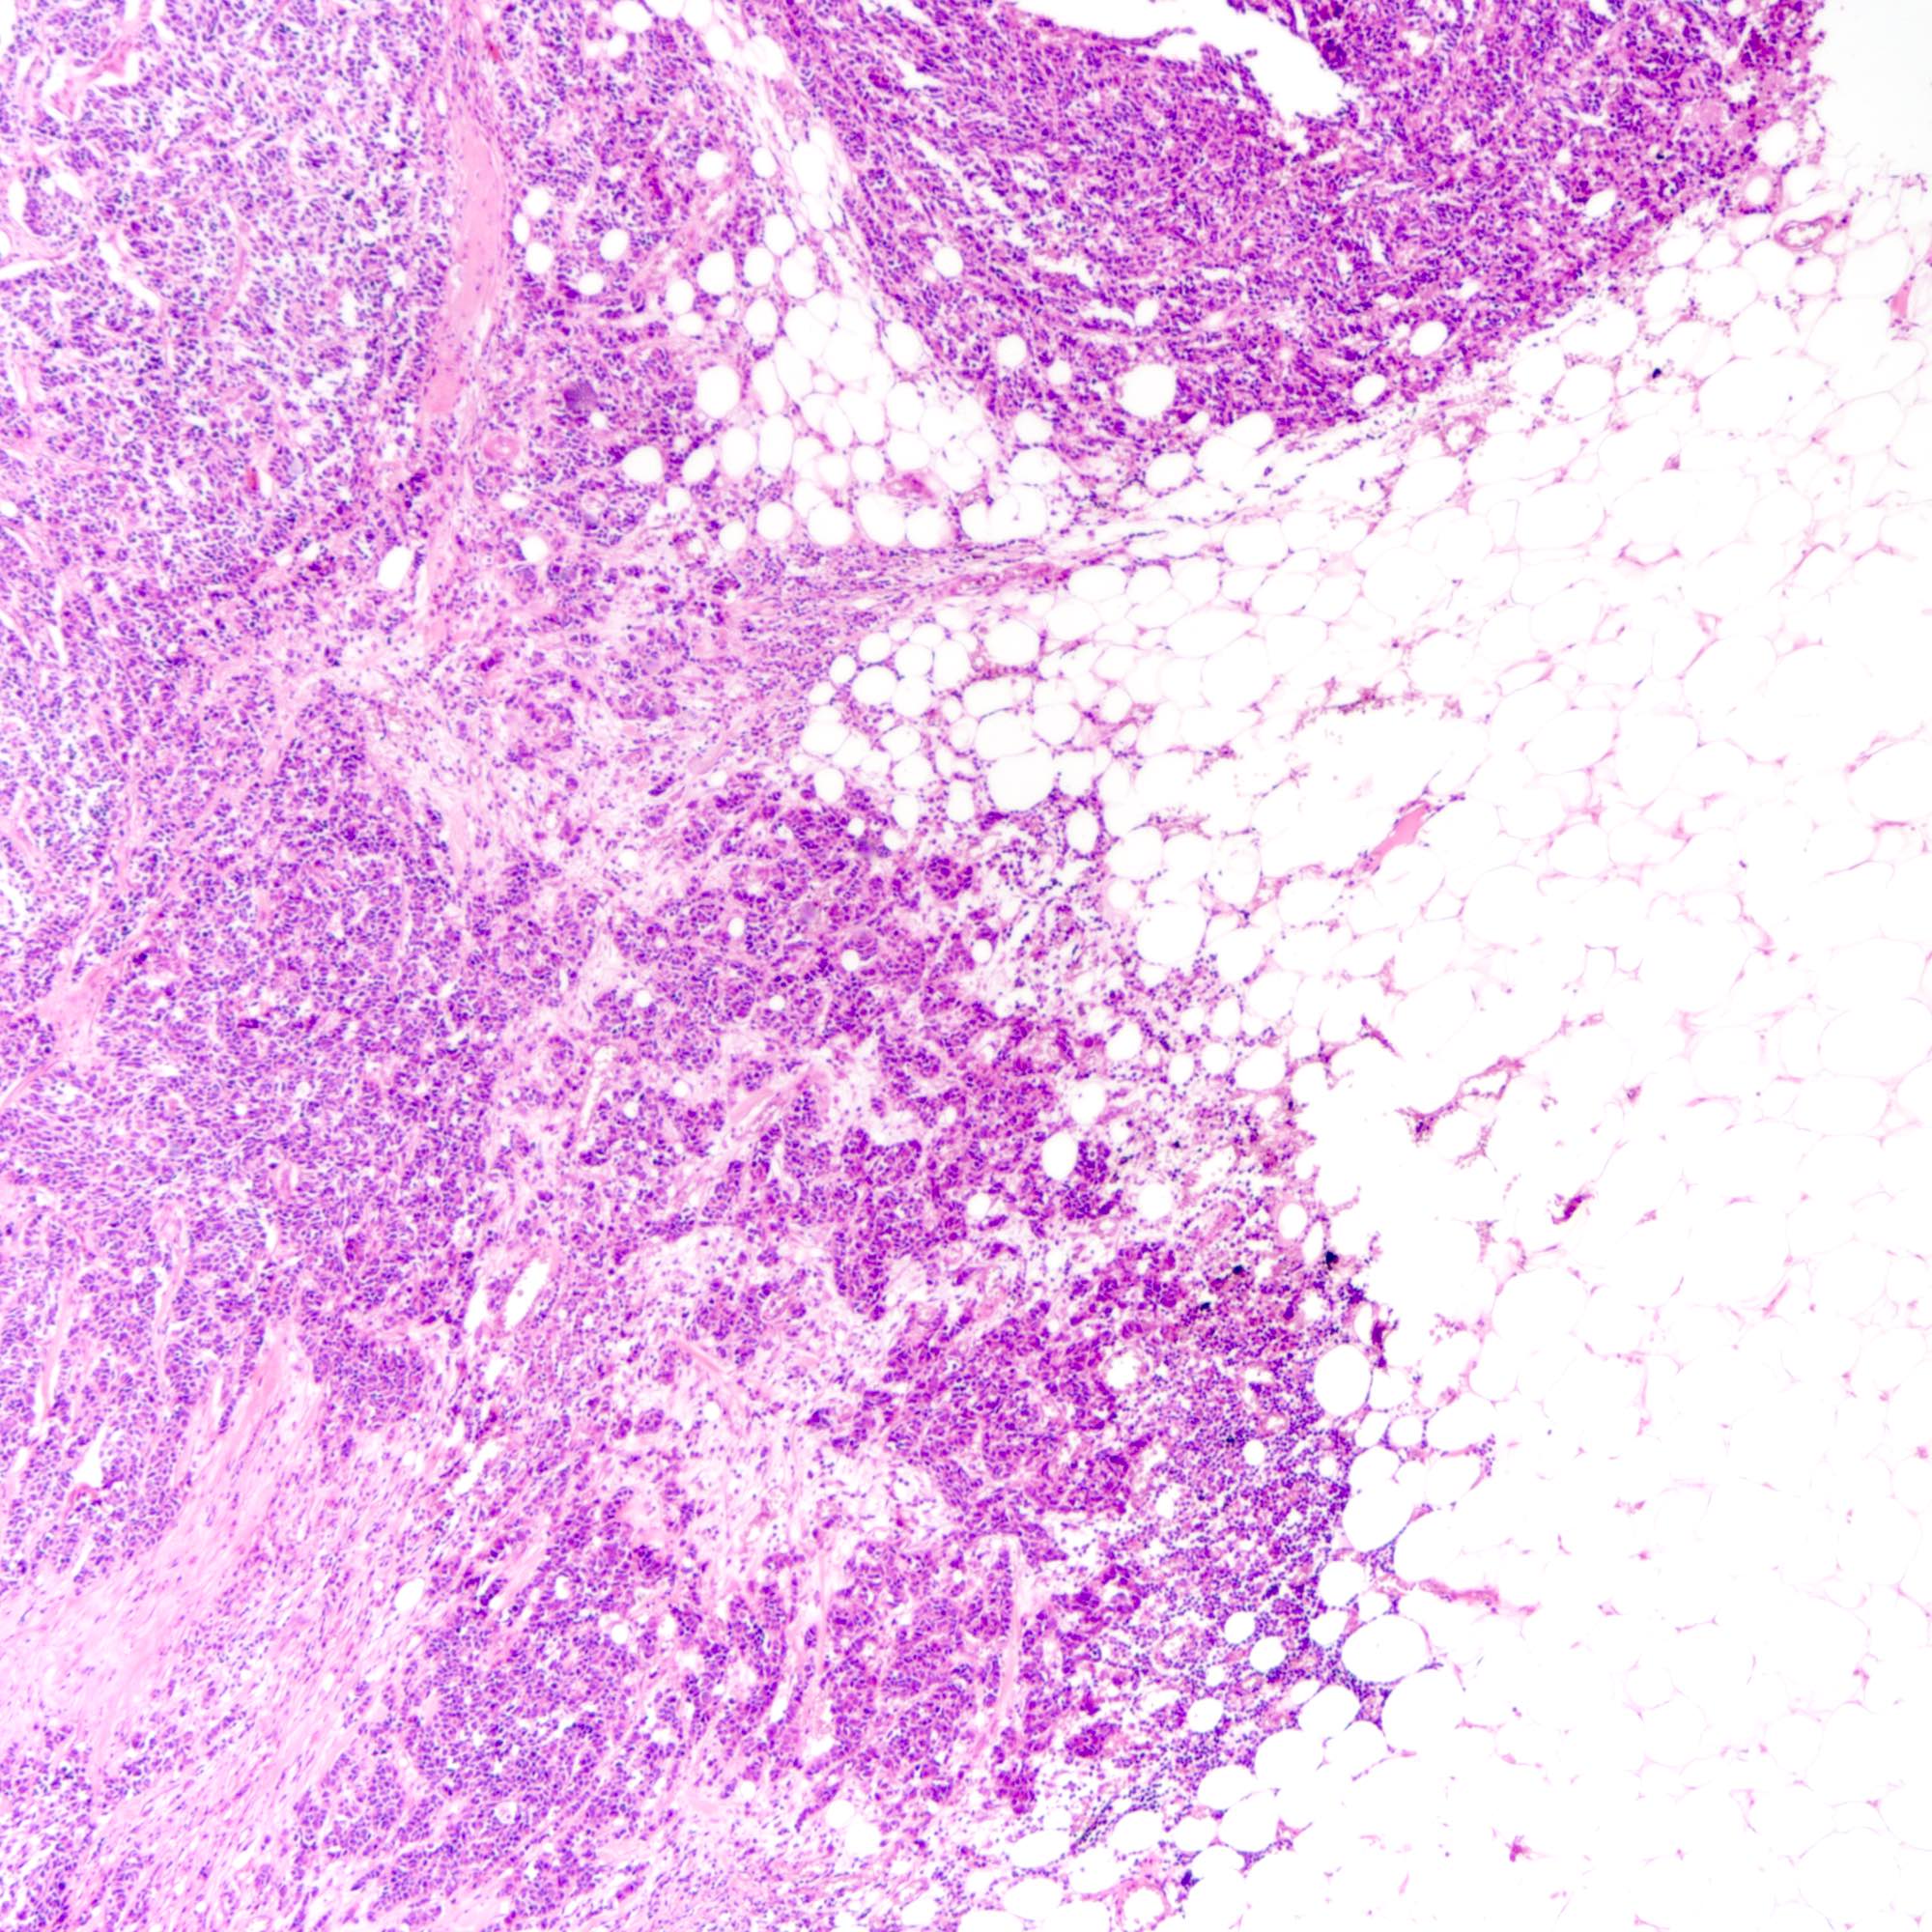

Microscopic (histologic) description

- Small cell carcinoma:

- Infiltrative growth pattern

- Crush artifact frequent

- Necrosis and lymphovascular invasion common

- Associated with proliferative changes, in situ carcinomas and invasive carcinomas (Am J Surg Pathol 2000;24:1231)

- In situ small cell carcinoma present in 5 out of 9 cases in a case series

- In situ / invasive ductal, lobular and squamous neoplastic components occasionally identified

- Infiltrative growth pattern

Microscopic (histologic) images

Contributed by Joshua J.X. Li, M.B.Ch.B., Gary M. Tse, M.B.B.S. and Kristen E. Muller D.O.

Small cell carcinoma